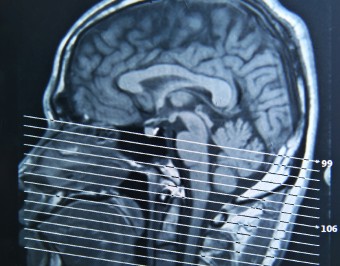

Imaging studies can be useful to show the internal extent of deep tumors and the presence of abnormal lymph nodes that may be difficult to detect. CT (computed tomography) and MRI scans give the most detailed information. More recently, PET (Positron Emission Tomography) scans employ nuclear medicine and digital technology to detect early recurrent cancer or metastases to other organs. The PET scan is particularly useful in following patients after therapy.